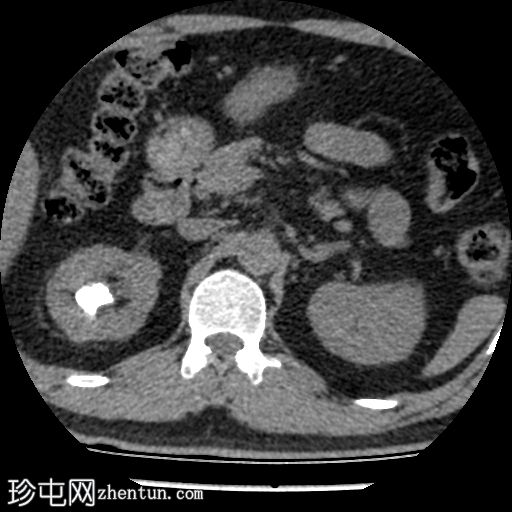

CT

轴位(非增强)

右肾上盏内可见一中等大小的结石,大小约为16 x 13 x 15 mm。右肾中盏内可见一小结石,大小约为4 x 2 mm。右肾下盏内可见另一小结石(过小无法测量)。未见肾盂肾盏扩张。

非增强 CT KUB 显示右肾多发结石,其中上肾盏结石较大,大小为 16 x 13 x 15 mm,密度较高(平均约 1060 HU),符合钙结石的特征。中肾盏和下肾盏可见其他较小的结石。

肾盂肾盏系统未见扩张,提示无梗阻性病变。该发现与患者反复腰痛的病史相符,腰痛可能与结石移位有关,而非当前存在梗阻。